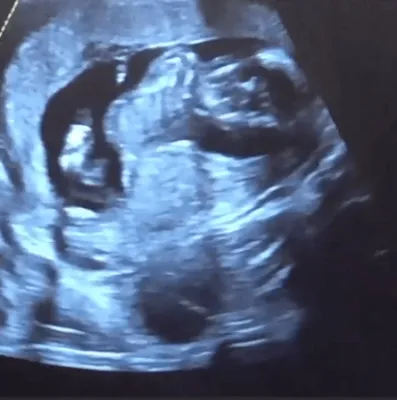

Le sue curve materne la rendono ancora più bella e sensuale. Da quando è in dolce attesa del suo primo bambino dal marito Sebastian Bear-McClard, mostra costantemente ai suoi fan il pancino che cresce e le curve che diventano col passare dei mesi sempre più esplosive.

Foto Instagram